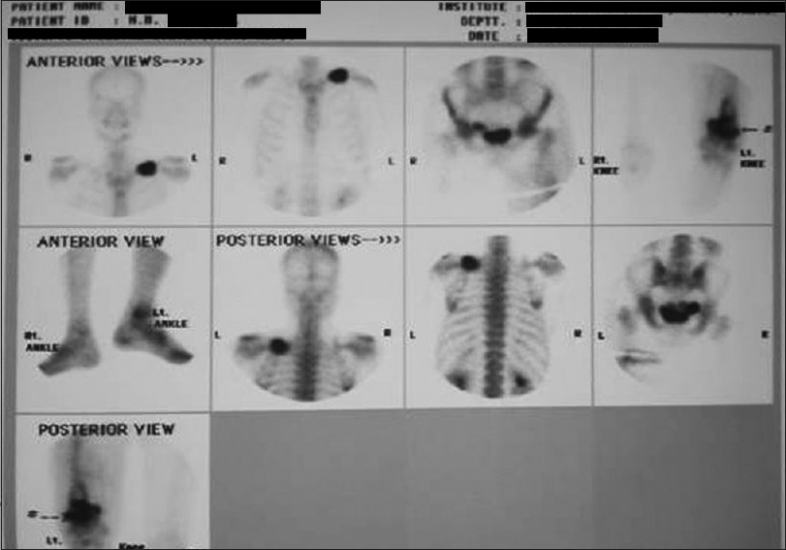

Skiagram of postero-anterior view of the chest revealed a fracture of the left clavicle [Figure 2]. Computerized tomography (CT) scan of the thorax was also advised, but the patient was unable to afford it. X-ray of the left limb showed a circumscribed lytic lesion in the lower shaft of the left femur. A whole-body bone scan (isotopic skeletal survey) with 99 m technetium-methylene diphosphonate revealed abnormally increased uptake over the left clavicle and distal end of left femur [Figure 3]. CT scan of the whole abdomen revealed multiple ill-defined hypodense enhancing space occupying lesions of varying sizes involving both lobes of the liver [Figure 4]. There was a 7.9 × 6.8 cm irregular heterogenous enhancing lesion of the left adrenal gland displacing the upper pole of the left kidney. The adrenal gland of the right side showed no abnormality. There was no retroperitoneal lymphadenopathy. ECG was within normal limits.

| Figure 3 Whole-body bone scan using Tc 99 m showing increased uptake by left clavicle and distal third of left femur